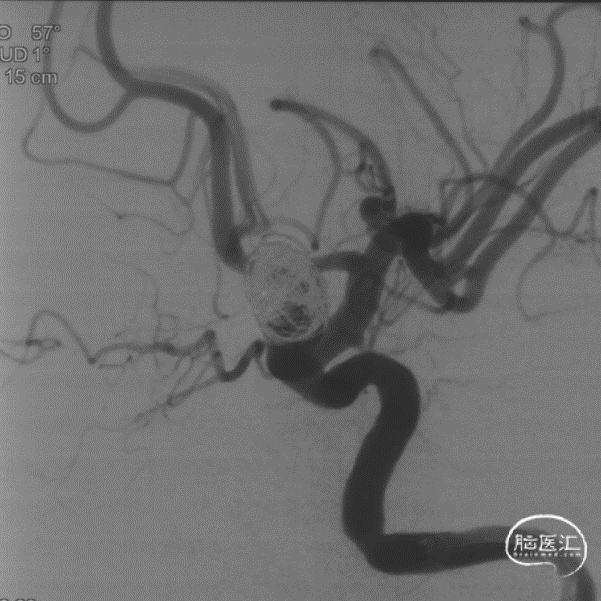

造影评估证实左侧眼动脉段动脉瘤,标记测量动脉瘤最大径13mm,动脉瘤颈5.6mm;近端血管直径4.3mm,远端3.8mm,后交通至海绵窦段后部长度24mm。压颈显示前交通开放。

选择合适工作角度。

选择Evolve 4.5/20,输送到位,通过推拉结合方式释放。

支架远端定位于脉络膜前动脉以近,近端位于海绵窦段。

动脉瘤大部栓塞,瘤颈部造影剂滞留。

Vaso CT重建 支架打开、贴壁良好。